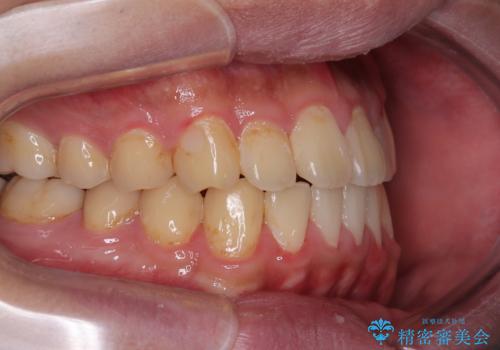

- 前歯のデコボコとクロスバイトを気にして来院された患者様です。

クロスバイトはありましたが、叢生の程度としては酷くなかったため、ワイヤー矯正でもマウスピース矯正でも、好きな方を選択していただきました。

治療開始前は汚れが多く、全体的に歯肉が腫れていましたが、矯正治療を通して腫れも少しずつ改善されました。